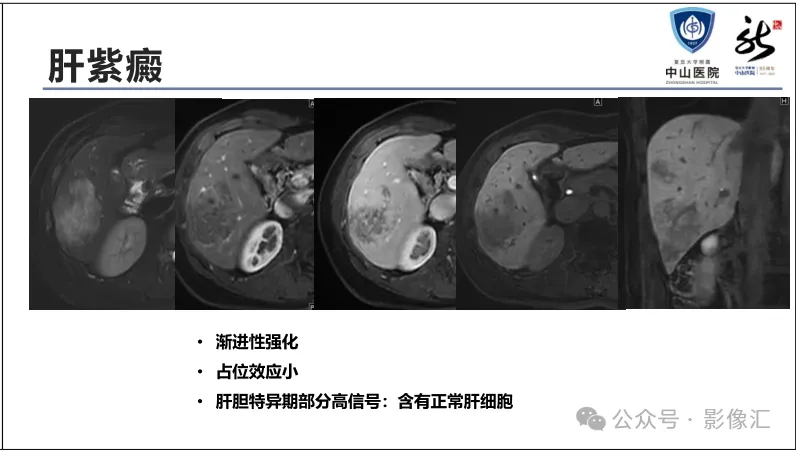

肝胆特异性对比剂增强肝胆图像判读方法与策略,课件来源于网络,作者复旦大学附属中山医院放射科饶圣祥教授。